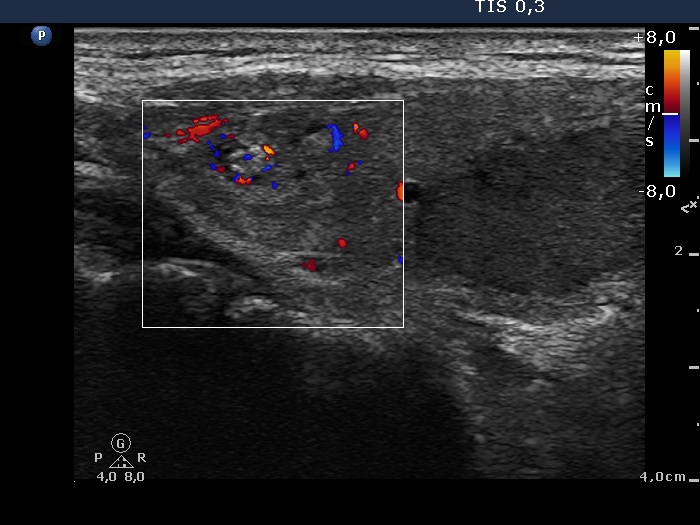

Consecutively operated patients with autoimmune thyroid disease - case 50 (408) (ultrasonographic picture 5)

Upper part of the right lobe, longitudinal view, color Doppler mode. The vascularization of the extranodular part has no relevance.